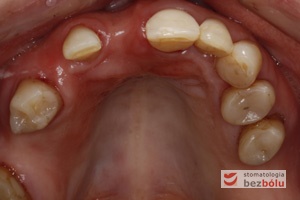

Zęby dolne powierzchnie okluzyjne - brak drugiego przedtrzonowca po stronie prawej - wady zębowe - rotacje i inklinacje

Zęby dolne powierzchnie okluzyjne – brak drugiego przedtrzonowca po stronie prawej – wady zębowe – rotacje i inklinacje